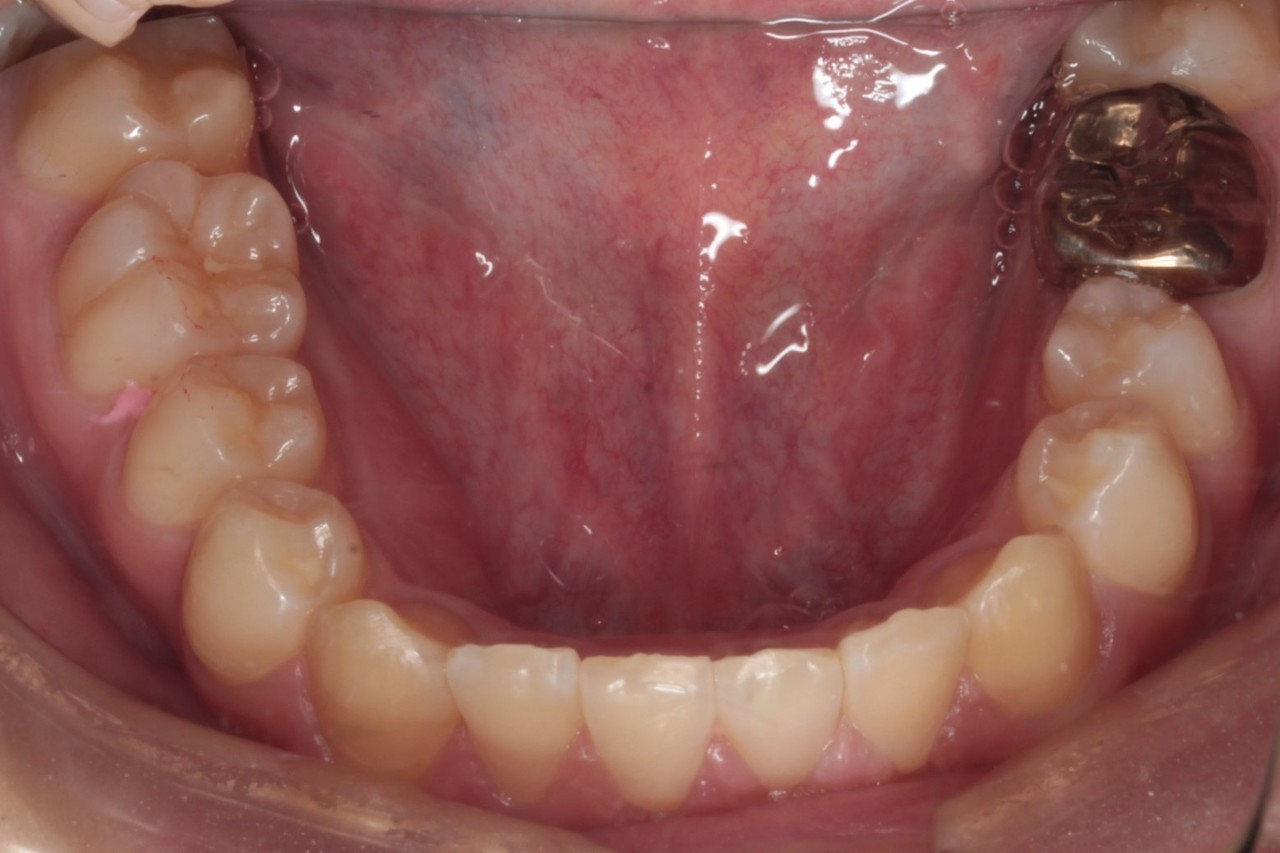

下顎 治療前

下顎 治療後

今回の症例は写真のように上の中心から2番目の歯が左右とも奥に入り込んでいてかなりスペースのない状態でした

にもかかわらず今回は非抜歯矯正での対応となります

非抜歯矯正で十分に並べられるという確信の元で行っております

非抜歯矯正では並べるスペースを得るのに

①遠心移動②IPR という2つのテクニックを用います